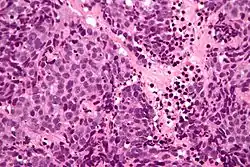

Micrograph of a sinonasal undifferentiated carcinoma. H&E stain. | |

Low mag.

High mag.